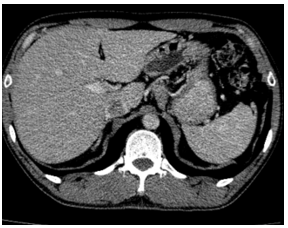

-         CT ổ bụng:

Hình 3. Trên phim chụp CT ổ bụng: Nhu mô gan sát bao gan phân thùy S5 có nốt giảm tỷ trọng trước tiêm, ngấm thuốc kém sau tiêm, đường kính 10mm – Theo dõi tổn thương thứ phát. Dày tuyến thượng thận trái.

Trên phim chụp cắt lớp vi tính ổ bụng:

Trước điều trị:

Sau 3 tháng điều trị: Tổn thương gan và thượng thận đã biến mất.

Hiện tại trong quá trình theo dõi gan và thượng thận 2 bên vẫn chưa xuất hiện tổn thương mới.